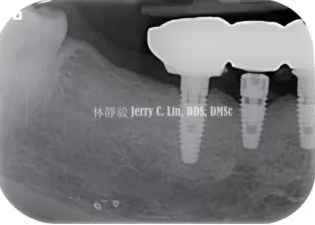

嚴(yán)重種植體周圍炎的處理(二)——林靜毅醫(yī)師